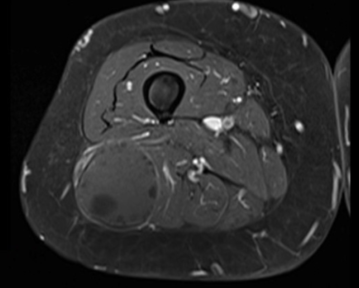

Se presenta el caso de una paciente de sexo femenino de 70 años, procedente de zona rural con diagnóstico clínico imagenológico de quiste hidático primario músculo-esquelético en muslo. La resonancia magnética (RM) (figura 1) y (figura 2) evidenciaba la presencia de una lesión isointensa en T1, de aspecto quístico, en el espesor del músculo bíceps femoral, inmediatamente por detrás del tabique intermuscular lateral. En la (figura 1) se evidencia corte axial de RM en secuencia T1 con saturación de la grasa. Se puede apreciar la relación en profundidad con ramas de las arterias perforantes, colaterales de la arteria femoral profunda. En la (figura 2) se evidencia corte coronal de RM en secuencia T1 con saturación de la grasa con gadolinio que evidencia realce de la pared y algunos septos incompletos. La tomografía computada no evidenciaba enfermedad a nivel hepático y/o pulmonar. La paciente había recibido tratamiento previo con albendazol.

La imagenología constituye un pilar diagnóstico fundamental, destacándose el uso de la ecografía, tomografía computada (TC) y RM (68% vs. 32% vs. 72%). De la revisión, en más de la mitad de los pacientes (n=15, 60%) se solicitaron dos estudios de imagen complementarios. La RM fue el estudio más solicitado, formando parte del algoritmo diagnóstico de las tumoraciones de partes blandas. Permite determinar el tamaño del quiste, y fundamentalmente sus relaciones musculares, vasculares y nerviosas, siendo una herramienta clave a la hora de planificar abordaje y táctica quirúrgica8,9. El quiste hidático se visualiza como una lesión quística cuya pared es hipointensa en comparación con el líquido intraquístico en secuencia T1. Es frecuente el hallazgo de vesículas prolígeras en su interior, como se observa en las (figura 1) y (figura2), que en T1 son hipointensas respecto a la matriz del quiste9. Se ha descrito en esta topografía la presencia del signo del camalote (water-lily sign), clásicamente comentado para quistes hepáticos o pulmonares. Puede verse edema perilesional por compresión o reacción inflamatoria de los tejidos adyacentes10. En todos los pacientes se asoció una ecografía de abdomen y/o tomografía de tórax y abdomen a fin de descartar enfermedad hepática o pulmonar sincrónica.